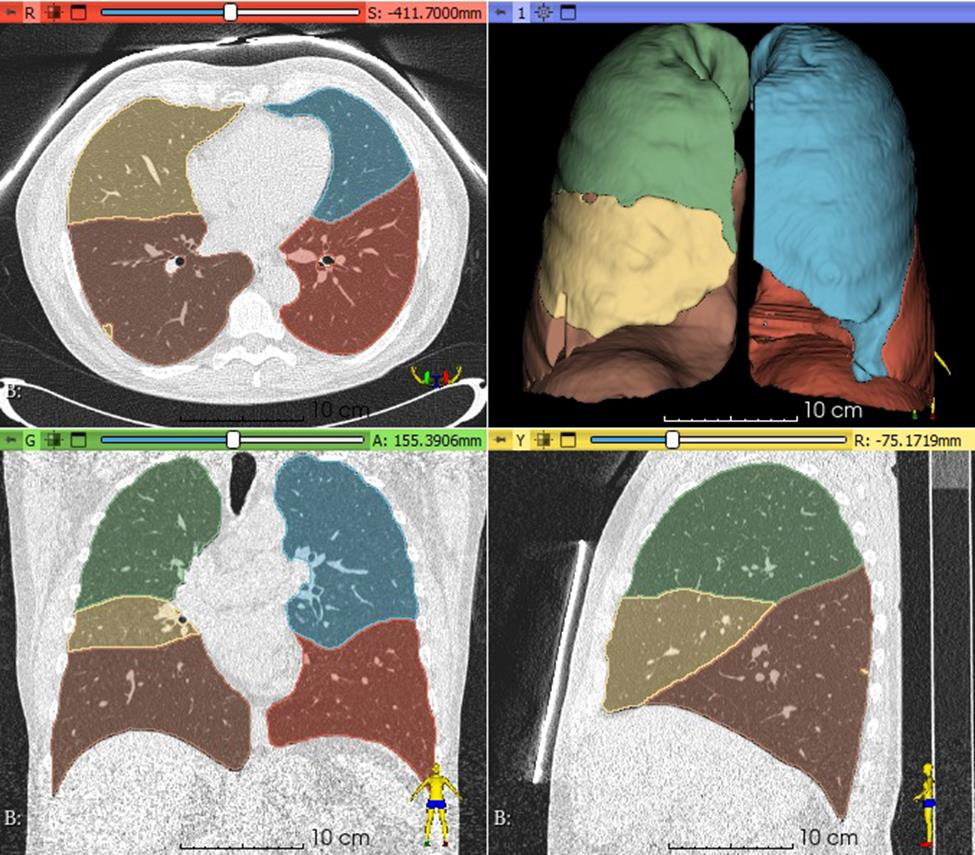

The International Association for the Study of Lung Cancer (IASLC), Accumetra, and numerous international CT lung cancer screening researchers published a paper in the Journal of Thoracic Oncology (JTO) showing that the open source Early Lung

Imaging Confederation (ELIC) system can support deep learning AI and quantitative imaging analyses on diverse and globally distributed cloud-based datasets. This paper provides results from deep learning and quantitative imaging experiments performed on 697 lung cancer screening cases with two CT image acquisition time points each. ELIC is designed to support the computational study of large collections of early lung cancer cases, where image data stays on the cloud within local regions while AI and quantitative imaging algorithms are distributed to those data locations. To read more about how this new global infrastructure can advance medical AI visit: ?.